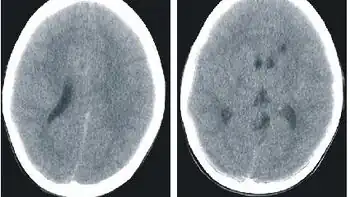

.jpg.webp)

Histidenemia is characterized by increased levels of histidine, histamine and imidazole in blood, urine and cerebrospinal fluid. This also results in decreased levels of the metabolite urocanic acid in blood, urine, and skin cells.[1]